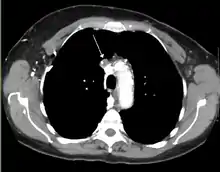

Діагностика

Основними методиками діагностики СВПВ є рентгенографія органів грудної клітки, КТ, трансбронхіальна аспірація під час бронхоскопії та медіастиноскопія.[8] Рентген часто дає можливість побачити основну причину СВПВ. Однак 16 % людей із СВПВ мають нормальний рентген грудної клітки. КТ слід посилити контрастом і робити на шиї, грудях, нижній частині живота та тазі. Вони також можуть показати основну причину та ступінь прогресування захворювання.